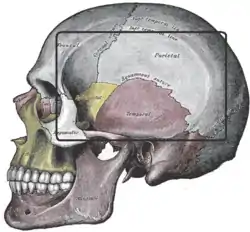

The temporal fossa is clearly visible in this picture | |

The temporal fossa is a fossa (shallow depression) on the side of the skull bounded by the temporal lines above, and the zygomatic arch below. Its floor is formed by the outer surfaces of four bones of the skull. The fossa is filled by the temporalis muscle.

- Medial/floor: frontal bone, parietal bone, (squamous part of) temporal bone, and sphenoid bone. The floor of the fossa features the pterion (the junction of these four bones).[1]: 357

- Lateral/roof: temporal fascia.[1]: 357

- Anterior: (posterior surface of) the frontal process of zygomatic bone, (the posterior surface of) the zygomatic process of frontal bone, and the maxilla.[1]: 357

- Superior: Pair of temporal lines (superior and inferior temporal lines) that arch across the skull from the zygomatic process of the frontal bone to the supramastoid crest of the temporal bone

- Inferior: zygomatic arch laterally and by the infratemporal crest of the greater wing of the sphenoid medially.